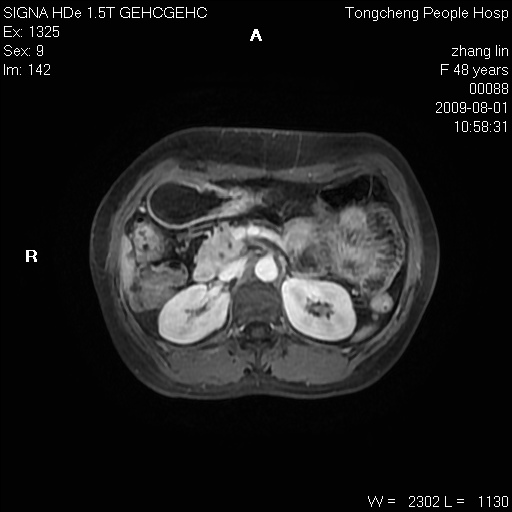

女,48岁。健康体检,彩超发现右肾占位性病变。平素健康。

临床诊断:右肾占位性病变,性质待定(囊肿?肿瘤?)。

上中腹部mr平扫+增强扫描,图像如下:

右肾上极见一类圆形病灶,t1wi呈等信号t2wi呈等高混杂信号,三期增强无强化,边界清---考虑囊肿出血。

同反相位均表现为等信号,病变无强化,考虑含蛋白的囊肿可能,弥散加权相或许有些帮助,